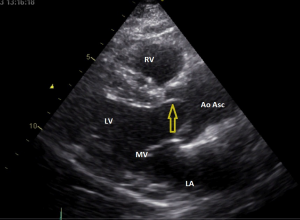

Video 2: echocardiografie korte as opname aortaklep (PSAX), zie ook figuur 3

Op de korte as opname ziet u dat de aortaklep wel degelijk uit twee klepblaadjes bestaat. Het stilstaand plaatje tijdens systole doet denken aan een vissenbek. Er moet dus sprake zijn van een bicuspide aortaklep

Figuur 3: Een stilstaand plaatje van video 2